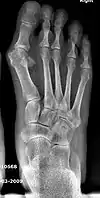

Bunion (hallux valgus) deformity is actually part of a complex of anatomical derangements of protruding mass (bunion), buckling of big toe (hallux valgus) and the bone behind it (metatarsus primus varus), displaced sesamoid bones (detrimental to the important walking function of big toe), collapsed metatarsal arch and several other secondary changes that are the domino effects of metatarsal primus varus. Thus, metatarsus primus varus correction has become the primary objective of all bunion surgeries.

Primus varus deformity

Primus varus deformity is the leaning of the first metatarsal bone away from the second metatarsal and towards the opposite foot (Fig. 1). As it leans over, its head sticks out to form the bunion bump and it also widens the forefoot to cause shoes feeling too tight. Thus when bunion pain becomes unmanageable, surgical correction is to narrow the forefoot by repositioning of the first metatarsal head back to its normal position. This can be done by osteotomy (bone-breaking), soft tissue (non-osteotomy) or fusion techniques.

Syndesmosis procedure addresses specifically the two fundamental problems of metatarsus primus varus deformity that gives rise to the bunion deformity. They are leaning and instability of the first metatarsal bone . Syndesmosis procedure uprights the leaning first metatarsal bone with strong binding sutures between it and the second metatarsal bone (Fig. 2) and then also stabilizes it uniquely by creating a fibrous connecting bridge between these two bones (Fig. 3, 4). First metatarsal bone can be readily realigned because by definition of the metatarsus primus varus deformity its first metatarsal is abnormally loose and mobile.